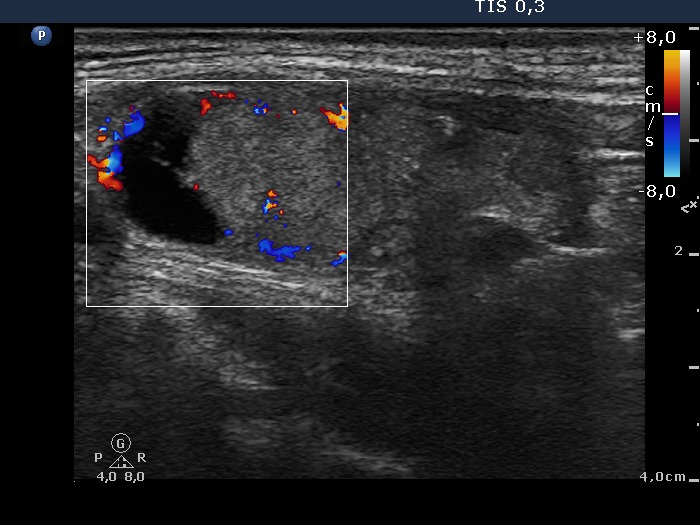

Right lobe, longitudinal scan

Right lobe, longitudinal scan, color Doppler mode. The cystic nodule presents perinodular blood flow.